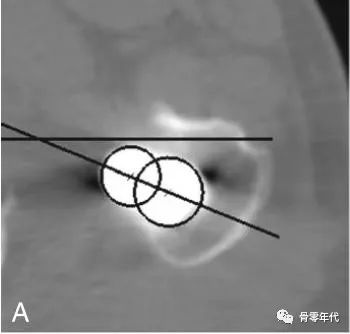

髓腔锉的前倾角:在扩髓至最后的髓腔锉肩部,保留该髓腔锉,屈膝使小腿垂直于地面,用量角器测量髓腔锉的前倾角。

股骨假体前倾角(A)计算为假体股骨颈相对于上髁线的夹角(B)。

髋臼杯前倾角(C)定义为在矢状面上测量的前倾角